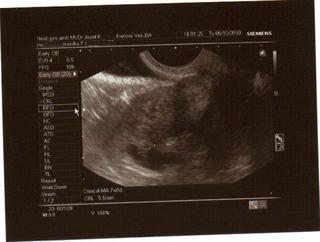

tak môj dnešný zážitok a sono...

prišla som k dr vysmiata hihi haha a idem do kabínky a vyzliekam sa a čo nevidím.. krv na intimke.. ja som tak začala plakať a modlila som sa k bohu tak ako ešte asi nikdy... Dr. asi po 10 minútach (konečne) otvoril dvere a keď ma zbadal tak hneď že čo je? tak mu vravím čo sa stalo a on, že aká krv? červená či hnedá, je jej veľa? Tak mu vravím, že hnedá a nie je toho veľa len také ako keby špinenie. tak on, že nech sa vyzlečiem, že ma pozrie. Pozeral ma teda aj hmatom aj sono robil. pri tom sone sa tak divne zatváril, zadíval sa na ten monitor, pozrel bližšie a zrazu mi to začal natáčať. Baby ja som myslela, že zomriem... a zrazu, že aha tu je srdiečko 🙂

Vraj je všetko O.K. a že to sa stáva každej druhej žene a hlavne tým čo si pichajú ten fraxiparine čo si pichám aj ja. Tak mi dal ešte jedny lieky (neviem na čo sú) a vraj mám byť úplne kľudná, že všetko je O.K. budúci utorok ideme na prvé tehu odbery a ten ďalší mi už na 100% dá aj knižku..

a tu je náš bubáčik.. povedal mi doki, že foto nič moc, lebo nechcel tlačiť na neho ale že kašlať na foto, hlavne, že vieme že malinké žije 🙂

Povedal, že je tam 100% pohyb a Gratuloval mi už 😉